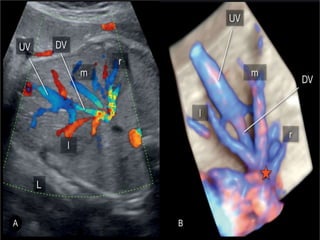

Ultrasound imaging and insonation

• A Sagittal anterior insonation offers the best

visualization of the Ductus venosus .

• An oblique transverse section may be more

convenient and easier to obtain in some fetal

position but rarely offers visualization of the

entire length of the vessel.

• Color Doppler is an indispensable tool to

identify the high velocity flow at the isthmus

of the ductus venosus.